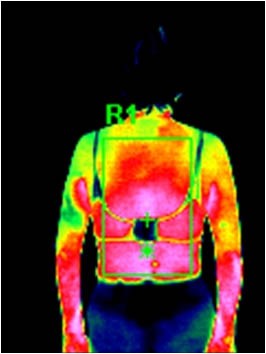

水素水風呂は冷え性の方にも効果があります。

サーモグラフィによる水素水風呂入浴後の実験データです。

水素風呂LitaLife 15分入浴後

| R1 | 平均温度 | 34.8℃ |

| R1 | 最高温度 | 36.9℃ |

| R1 | 最低温度 | 30.7℃ |